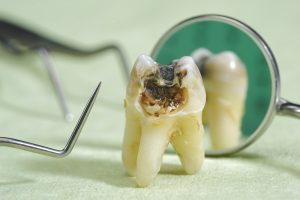

重度の虫歯

「虫歯くらいで…」と思われるかもしれませんが、穴が開くほど進行した重度の虫歯は、細菌の温床です。

特に、虫歯が歯の神経まで達してしまうと、歯の根の内部が細菌に感染し、これが全身への感染経路となるリスクをはらんでいます。

見た目にはそれほどひどく見えなくても、深い虫歯は神経の炎症や壊死を引き起こしている可能性があり、慢性的な感染源となりかねません。

このような歯は、手術前に神経の治療(根管治療)を完了させるか、状態によっては抜歯をして、細菌の元を断つ必要があります。